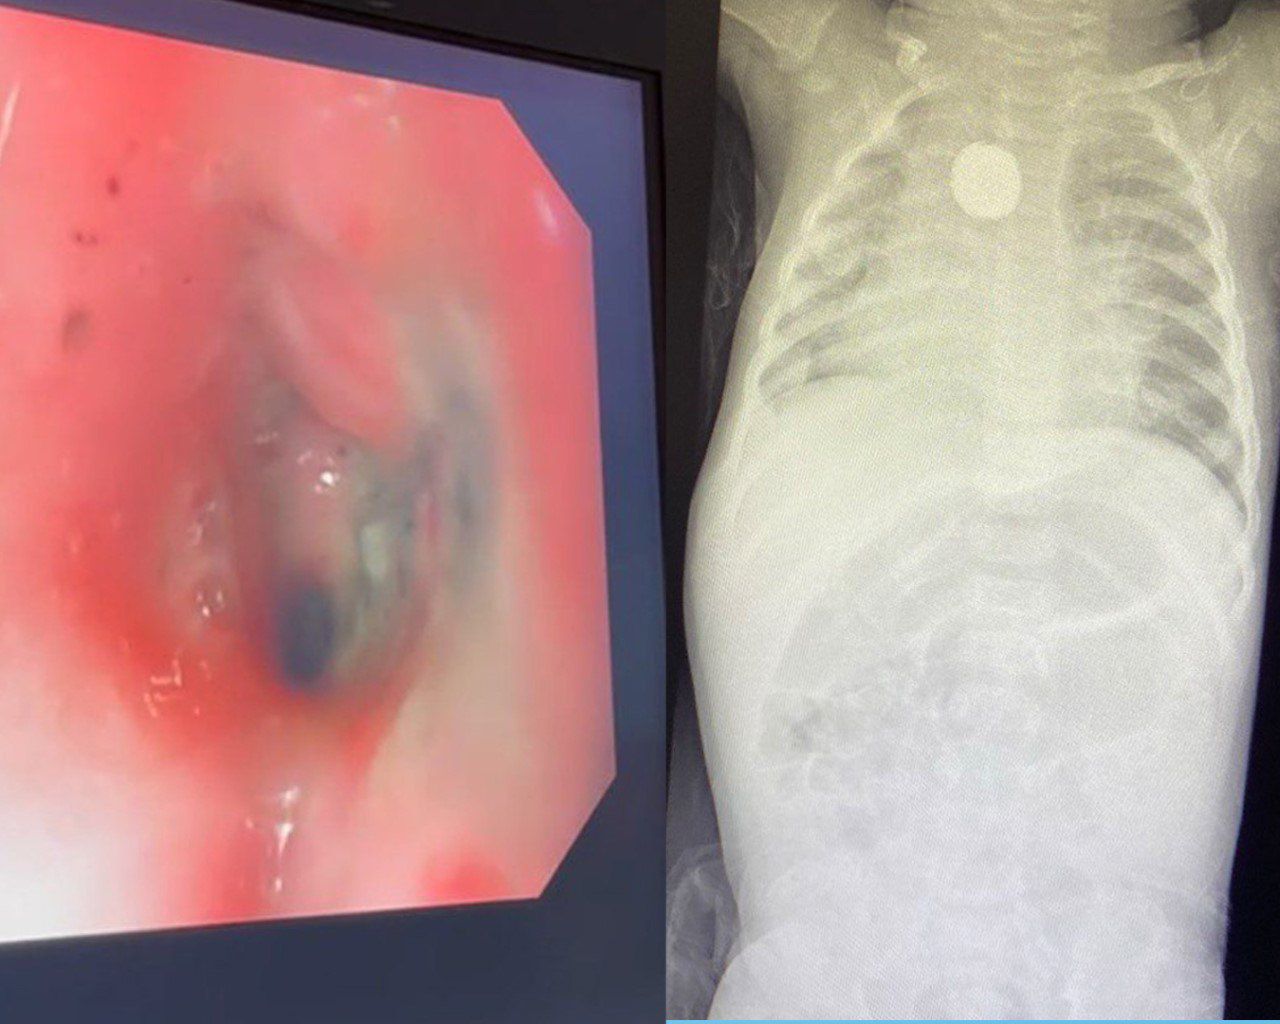

وأوضح تجمع مكة المكرمة الصحي، حضرت الطفلة إلى قسم الطوارئ كحالة إنقاذ حياة وهي تُعاني من التهاب متكرر في الحلق منذ شهر، ومع مضي الأيام أصبح البلع لديها صعب ولم تتمكن من البلع العادي منذ أكثر من خمسة عشر يوماً، وعلى الفور أجريت الفحوصات اللازمة حيث جرى اكتشاف جسم غريب مما استدعى التدخل الطبي العاجل لإنقاذ الطفلة، وتم تكوين ثلاث فرق طبية لاستخراج البطارية الحارقة دون حدوث مضاعفات، متمثلة في فريق قسم المناظير، وجراحة القلب والشرايين، وجراحة الأطفال، وتبين من خلال الأشعة المقطعية وجود الجسم الغريب على مقربة من شرايين القلب، مختفياً في جدار المريء مع الضغط على الحنجرة المجاورة.

وأضاف: تبين وجود حروق داخل المريء مع تضيق المنطقة المتأثرة وعدم رؤية الجسم الغريب مبدئيا وبعد عدة محاولات اتضح وجوده ملتصقاً ومغطى بأغشية الجدار داخليا، مما أتاح إمكانية سحبه بالمنظار بسلام دون حدوث ثقب أو نزيف في المنطقة ذاتها، وجرى إدخال المنظار مرة أخرى والتأكد من عدم وجود ثقب أو تسرب هوائي داخل الصدر